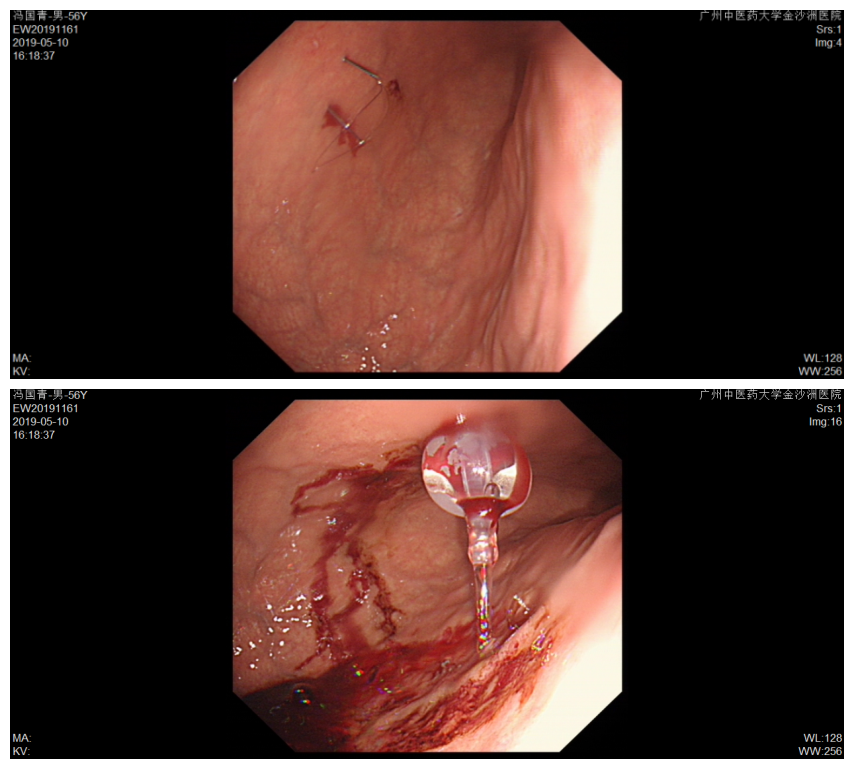

入院第三天,在我院内窥镜中心,胃镜下医生们给刘先生完成了胃造口术。术后刘先生的腹部多了一个小小的口子,一条细细的导管从这个口子连通到他的胃。观察24小时无异常,就可以经由这根导管往刘先生胃里直接打营养剂和打碎的食物了。

造瘘管内部观

管腔通畅,仅少许渗血